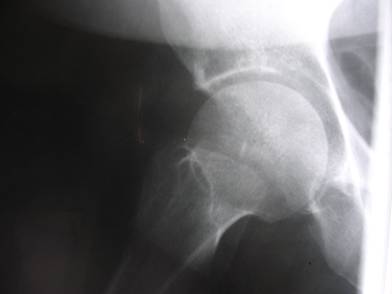

Chronic right hip pain